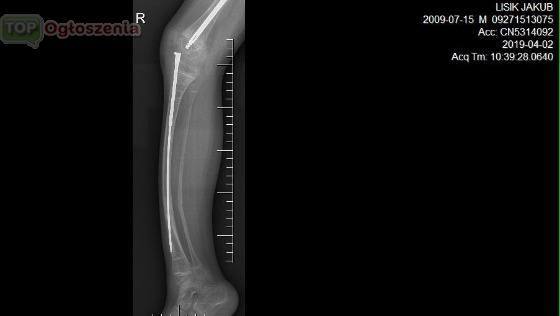

jest pacjentem Kliniki UDSK Białystok w

Której wszczepiono specjalny implant teleskopowy. Proteza rośnie wraz z dzieckiem i zapobiega ciągłemu łamaniu się kości. Operację przeprowadził Śp Wojciech Zalewski z Kliniki Ortopedii i Traumatologii Dziecięcej w Białymstoku . osteogenesis imperfecta, czyli wrodzona łamliwość kości.

Kubuś ma 9 lat . Od urodzenia jest pod opieką leczony farmakologlicznie ortopedycznie za sobą ma ponad 30 samoistnych złamań kości i kilka operacji przed Kuba następne zabiegi najbliższy 27 mają 2019 wyjazd do kliniki i wyznaczony zabieg wymiany implantu 29 maja 2019r przez dr Maciej Gerard Gendorff.

By zahamować postępy choroby przyjmują leki (bisfosfoniany) i wszczepia się im implanty do kości udowych i piszczelowych. Tel 511-417-140